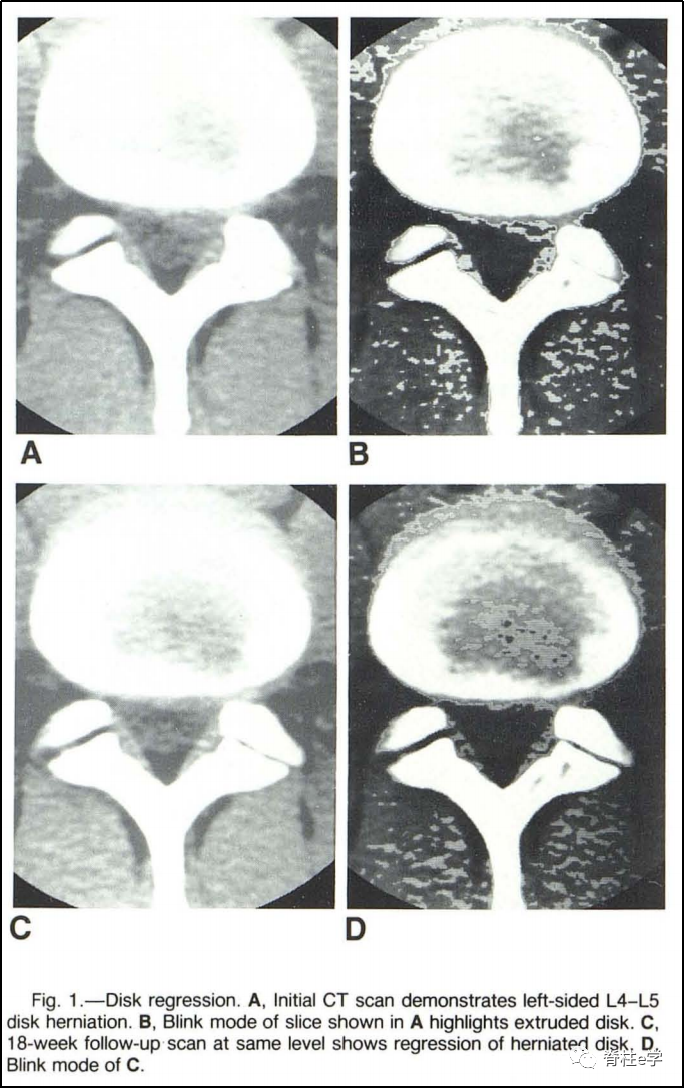

患者女,30岁,腰痛伴双下肢疼痛,无马尾受压症状。查体示:L4/L5和L5/S1双侧棘突压痛放射至双下肢,左侧、右侧直腿抬高试验50°(+)。双下肢皮肤感觉、肌力正常。图示:L4/L5椎间盘突出后再吸收,L5/S1椎间盘前后无变化。腰椎间盘突出后重吸收:是指腰椎间盘突出症患者未经手术治疗而发生的突出髓核消失或缩小的现象。对腰椎间盘突出后重吸收现象的研究,最早可以追溯到1984年,国外学者Guinto通过个案报道分享了一例腰椎间盘突出症患者保守治疗CT随访案例,首次发现突出的椎间盘组织可以缩小或者消失,并称之为“自发性消退”。

此后,国外关于椎间盘突出后重吸收现象的报道日益增多。国内研究是由姜宏教授于1998年率先报道腰椎间盘突出物具有“自然吸收”的转归趋势,在《中华骨科杂志》期刊发表了关于腰椎间盘重吸收的影像学观察及其机理研究的新进展的综述。